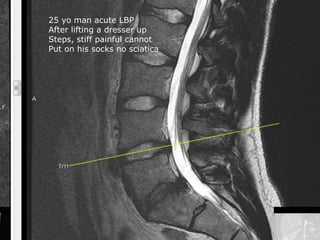

25 yo man acute LBP

After lifting a dresser up

Steps, stiff painful cannot

Put on his socks no sciatica

Disabling